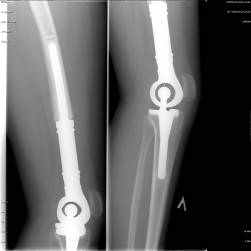

Рис. 1. Больной 18 лет. Диагноз: состояние после комбинированного лечения по поводу остеосаркомы нижней трети бедренной кости. Операция выполнена в объеме дистальной резекции бедренной кости с замещением дефекта эндопротезом коленного сустава. Рентгенограммы проксимального и дистального отделов эндопротеза. Оценка MSTS составила 87%; срок наблюдения – 54 мес.

Рис. 2. Больная 17 лет. Диагноз: состояние после комбинированного лечения по поводу остеосаркомы правой бедренной кости. Укорочение ноги составило 12 см. Операция в объеме тотального реэндопротезирования бедренной кости с замещением дефекта модульным раздвижным эндопротезом. Рентгенограммы проксимального и дистального отделов эндопротеза. Оценка MSTS – 72%; срок наблюдения – 42 мес.

Таким образом, эндопротезирование костей и суставов в клинической онкологии является эффективным методом, обеспечивающим достижение клинического выздоровления и благоприятного функционального результата. Органо-сохраняющие операции – это золотой стандарт современной онкоортопедии (рис.1-2).